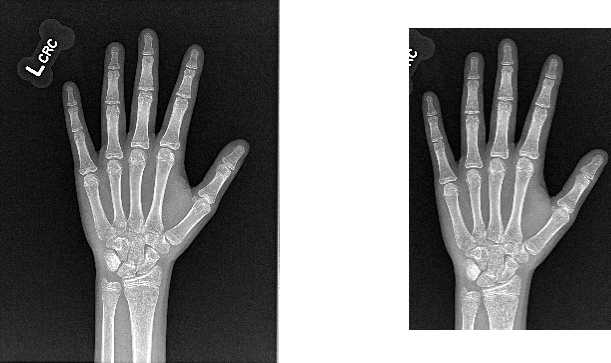

This model crops hand radiographs to better standardize the image input for bone age models.

The model uses a lightweight mobilenetv3_small_100 backbone and predicts normalized xywh coordinates.

The model was trained and validated using 12,592 pediatric hand radiographs from the RSNA Pediatric Bone Age Challenge using an 80%/20% split. On single-fold validation, the model achieved mean absolute errors (normalized coordinates) of:

x: 0.0152

y: 0.0121

w: 0.0261

h: 0.0213